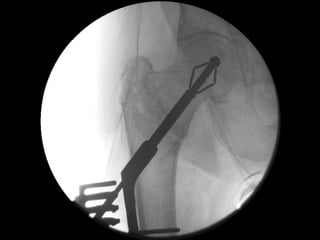

Perpendicular Expansion = No Disruption

Compacts bone = better stability

‘Tip-Apex’ distance

Tip-Apex Distance (combined >25mm) is a major factor in predicting cut-out

Baumgaertner et al. JBJS Am 1995; 77:1058-64